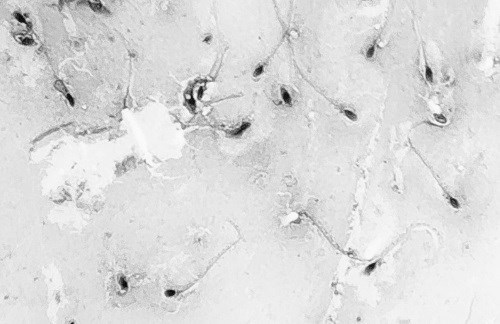

Придаток яичка состоит из крошечных и многократно сложенных трубочек. Если разложить эти трубочки в прямую линию, то их длина составит 6–7 м. Незрелые сперматозоиды хранятся в придатке яичка до созревания. Придаток яичка связан с семенными канальцами, которые проходят за мочевым пузырем и соединяются с семявыводящими канальцами, образуя семяизвергающий канал (см. рисунок на стр. 285). Кстати, при вазэктомии перерезаются именно семявыводящие канальцы. После эякуляции на восстановление «запасов» придатку яичка требуется около двух дней. Семенная жидкость В процессе эякуляции сперматозоиды проходят по семявыводящему каналу и смешиваются с жидкостью из семенных пузырьков, предстательной железы и бульбоуретральных, или куперовых, желез, образуя семенную жидкость. Все эти железы выделяют щелочную жидкость, которая повышает рН семенной жидкости для нейтрализации кислой среды женской половой системы. Кроме того, половые железы помогают активировать хвосты сперматозоидов и увеличить их подвижность. Семенные пузырьки. Эта пара желез вырабатывает большую часть жидкостей, входящих в состав спермы. Семенные пузырьки вырабатывают желтоватую жидкость, которая помогает в перемещении спермы и содержит сахара (фруктозу), питающие сперматозоиды. Кроме того, семенные пузырьки вырабатывают особые вещества – простагландины, облегчающие движение сперматозоидов по женским половым путям. Протоки семенных пузырьков сливаются с семявыносящими, образуя семявыводящий проток, который проходит через предстательную железу и открывается в мочеиспускательном канале. Половая клетка Идеальная температура для развития сперматозоида в яичках – на 1,7 °C ниже нормальной температуры тела. В мошонке присутствуют специальные мышцы, которые прижимают яички ближе к телу, если им необходимо согреться. Когда становится слишком жарко, мошонка расслабляет свои кровеносные сосуды, позволяя теплу рассеиваться. Длина одного сперматозоида – 0,05 мм. В зрелом возрасте передняя часть головки сперматозоида, или акросома, приобретает ферменты, позволяющие ему проникать в яйцеклетку. Средняя часть сперматозоидов заполнена митохондриями, которые вырабатывают энергию, необходимую для движения к яйцеклетке. Концентрация сперматозоидов в придатке яичка – около 300 миллионов клеток на 1 мл. Но даже у мужчин без проблем с фертильностью не все сперматозоиды идеально развиты. Некоторые сперматозоиды могут содержать две головки, одну крупную или деформированную головку или несколько хвостов. Сперматозоиды с двумя головками не смогут проникнуть в яйцеклетку, а клетки с другими патологиями могут привести к выкидышу. Сперматозоиды, не выделенные с эякулятом, распадаются и реабсорбируются. Многие сперматозоиды выводятся с мочой. ![]() Предстательная железа. Расположена в основании мочевого пузыря. Эта железа окружает мочеиспускательный канал и сокращается при эякуляции, выделяя в семенную жидкость свой молочно-белый секрет. Данный секрет разжижает семенную жидкость, облегчая движение сперматозоидов. ![]() Бульбоуретральные железы. Эти парные железы размером с горошину выделяют прозрачную щелочную жидкость, которая нейтрализует в мочеиспускательном канале любой кислотный остаток мочи, способный повредить семенную жидкость. Половой член Говоря о мужских половых органах, многие люди обращают внимание именно на него. Причем размер полового члена может быть как предметом гордости, так и поводом для расстройства. Основная функция полового члена, или пениса, состоит в том, чтобы доставить сперму глубоко во влагалище (а еще он служит наружным органом для выделения мочи). Кроме того, половой член позволяет мужчинам получать удовольствие даже без сексуального партнера. И для многих мужчин утреннее пробуждение с полностью эрегированным пенисом служит признаком хорошего состояния эректильной ткани. Утренняя эрекция – это последствие ночных эрекций, которые, как полагают ученые, происходят в фазу быстрого сна (REM-фазу). Половой член состоит из следующих частей. ![]() Это изображение семенной жидкости под микроскопом. Здесь четко различимы головки и хвосты сперматозоидов. Мочеиспускательный канал. Проходит по центру внутри полового члена. Это наружный канал для выведения мочи и спермы. Мочеиспускательный канал связан с мочевым пузырем через плотное мышечное кольцо, предотвращающее подтекание мочи. Семявыводящий проток и протоки семенных пузырьков открываются в мочеиспускательный канал рядом с местом, где он отходит от мочевого пузыря. Головка. Это самая чувствительная часть полового члена, особенно по краям (венечная борозда). Тело. Это основная часть полового члена. Она образована губчатой тканью – пещеристым и губчатым телами. Обе эти части при эрекции наполняются кровью. Длина тела пениса в состоянии покоя и эрекции различается, а также отличается у разных людей. В расслабленном (неэрегированном) состоянии полная длина полового члена составляет 6–12 см. Эрегированный пенис может достигать длины в 10–20 см. Корень. Это основание полового члена, которое прикрепляется к паху. Крайняя плоть. Это кожная складка, которая защищает головку полового члена при несексуальной активности. Иногда ее отсекают (во время обрезания). При эрекции крайняя плоть сдвигается. Кроме того, крайняя плоть вырабатывает естественную смазку – смегму, которая при нерегулярной гигиене образует творожистые выделения и способствует развитию воспаления. Женская анатомия Старинная английская поговорка гласит: «Мужчина работает от заката до рассвета, а женской работе нет конца». Это же можно сказать и о репродуктивных функциях, ведь женский вклад значительно больше. Женщина не только вырабатывает яйцеклетки для оплодотворения, но еще и несет ответственность за новую жизнь, зарождающуюся внутри нее. И готовиться к этой сложнейшей задаче тела девочек начинают заранее, поэтому пубертатный период у них наступает значительно раньше, чем у мальчиков. Яичники Это парные овальные структуры, расположенные с обеих сторон матки и зафиксированные с помощью эластичных связок. Длина яичников не превышает 3 см, а толщина – 1 см. Яичники служат местом созревания яйцеклеток, или плодных яиц, до их высвобождения в период овуляции. ![]() Женская половая система расположена глубоко внутри тела. В яичниках содержится около миллиона зародышевых яйцеклеток – этого количества женщине хватает на всю жизнь. Процесс создания яйцеклеток называют овогенезом, который включает в себя мейотическое деление половых клеток – гамет (см. «Мейоз» на стр. 36). В результате овогенеза в каждой яйцеклетке сохраняется половина от общего набора хромосом. |